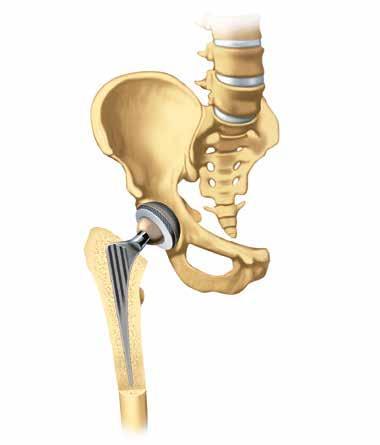

Remplacement articulaire Si l’arthrose a déjà fortement endommagé une articulation, la mise en place d’une prothèse peut aider à retrouver la qualité de vie perdue. Les douleurs et les fortes limitations des mouvements lors de la marche ou en position debout peuvent être atténuées, et souvent même complètement éliminées, et l’autonomie peut être restaurée.

Le terme technique utilisé pour désigner une articulation artificielle est « prothèse » ou plus spécifiquement « endoprothèse », du préfixe grec « endo » qui signifie « dedans ». L’endopro-

29

thèse désigne donc une prothèse artificielle implantée dans l’organisme, où elle demeure pendant une période prolongée.

Qu’est-ce qui m’attend ?

Les endoprothèses les plus fréquemment utilisées sont celles de la hanche, du genou et de l’épaule. Dans de nombreux hôpitaux, ces opérations sont des interventions de routine. Une articulation artificielle est constituée de plusieurs parties. La prothèse est généralement composée d’alliages de chromecobalt ou de titane. Les surfaces de glissement articulaire sont constituées de polyéthylène extrêmement résistant et de céramique.

Le cartilage endommagé de l’articulation doit être retiré avant la pose de l’implant. Le chirurgien

30 TRAITEMENT

ou la chirurgienne essaiera bien sûr de ne retirer que la masse osseuse strictement nécessaire.

Des prothèses partielles peuvent également être utilisées pour certaines articulations, par exemple le genou, quand seule une section limitée du cartilage articulaire est détruite.

Les hanches artificielles sont généralement posées au moyen d’une chirurgie mini-invasive. Dans cette méthode, l’incision cutanée est relativement petite et, contrairement aux méthodes traditionnelles, les muscles ne sont pas sectionnés, mais dilatés ou écartés. La perte sanguine est généralement faible et les patient·e·s se remettent plus vite de l’opération. Il existe cependant des facteurs qui plaident en faveur des méthodes traditionnelles, par exemple un surpoids important, des opérations ou maladies antérieures, un risque

de thrombose ou des déformations osseuses. Le ou la médecin décidera au cas par cas du procédé le plus adapté.

Les prothèses doivent être solidement fixées à l’os pour assurer un bon maintien. Les spécialistes parlent « d’ancrage ». Cet ancrage peut être réalisé de deux manières : cimenté et non cimenté. Le choix de la méthode par la chirurgienne ou le chirurgien orthopédiste dépend notamment de la maladie et de l’état de l’os et la décision définitive est prise au cours de l’intervention, la structure osseuse étant déterminante.

Prothèses cimentées : elles sont fixées à l’os par un plastique à durcissement rapide, le ciment osseux, un peu comme par de la colle. Elles conviennent généralement aux personnes âgées qui ont les os plus fragiles. L’avan-

tage : l’articulation peut être à nouveau sollicitée assez rapidement.

Prothèses non cimentées : les implants présentent une surface particulièrement rugueuse qui permet l’implantation en facilitant l’intégration de la prothèse à l’os. Mais il faut pour cela que l’os ait encore une vitalité et une solidité suffisantes pour offrir suffisamment de stabilité à l’implant. Aujourd’hui, la plupart des prothèses de la hanche sont non cimentées. À l’inverse, on a le plus souvent recours au ciment osseux pour les prothèses du genou.

Cotyle

la musculature : elle fournit également aux patient·e·s toutes les informations importantes sur les séquences de mouvements et élabore un programme d’entraînement spécifique, qui peut ensuite être poursuivi à la maison. Quelle est la durée de vie d’une prothèse articulaire ?

La durée de vie d’une endoprothèse dépend de nombreux facteurs. Dans des conditions favorables, on table sur une durée de vie de 15 à 20 ans pour certaines hanches artificielles et de 15 ans pour certaines prothèses du genou. Des études font état de durées de vie de 10 ans et plus pour certaines prothèses de l’épaule. Ces résultats ne peuvent toutefois pas être généralisés. Dans un cas défavorable, il peut également arriver qu’un implant doive être remplacé beaucoup plus tôt, par exemple en cas de complica-

tions suite à une chute ou une infection. Une prothèse peut en principe être remplacée plus d’une fois, mais les interventions de remplacement sont généralement beaucoup plus complexes que l’intervention initiale.